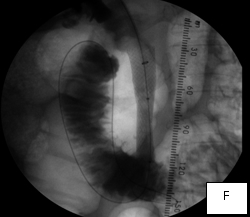

The second case was a woman with obstructive jaundice from cancer of the head of the pancreas, which produced a tapering narrowing of her common bile duct. In her, I crossed the diseased duct by cannulating a right intrahepatic duct from a right percutaneous puncture. Once I secured the access with a sheath, I was able to cross the obstruction with a stiff glidewire (image D) over which I deployed a Wallstent (image F).